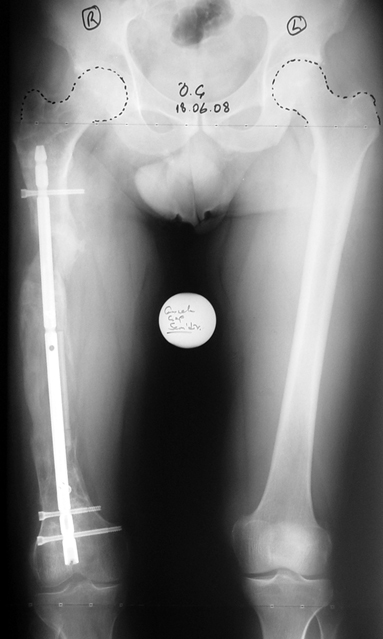

The duration of external fixation (external fixation index) depends on the amount of distraction required, and the extremity is prone to complications during this period. After the distraction phase is completed, the external fixator remains in place during the consolidation phase, which lasts twice as long as the distraction phase; but this period is hardly tolerated. If the external fixator is removed before sufficient consolidation is achieved, fractures, deformity and shortness will be the result. In our department, ‘lenghthening over nail’ method is used in order to decrease the external fixation index and increase patient comfort and activity level. In this method, the intramedullary nail is statically locked after the completion of the distraction phase, and external fixator is removed. The extremity is stabilized by the intramedullary nail during consolidation phase. In this way, complications due to long external fixation index or early removal of the external fixator are avoided.

Case 1